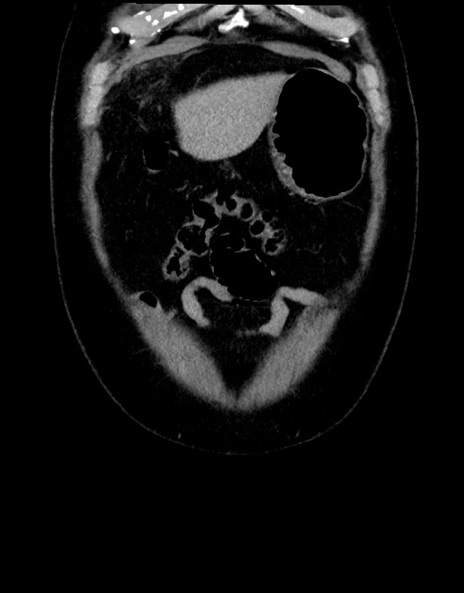

症例15(冠状断像)

【症例】70歳代男性

【主訴】腹痛

【現病歴】今朝から腹痛あり。全体的に痛い。特に左上の方。排ガスが今日はない。冷や汗が出る。

【既往歴】直腸癌術後

【身体所見】左側腹部〜上腹部に圧痛あり。腹膜刺激症状明らかなではない。軽度反跳痛。左下腹部に術後瘢痕あり。

【データ】WBC 7700、CRP 0.02